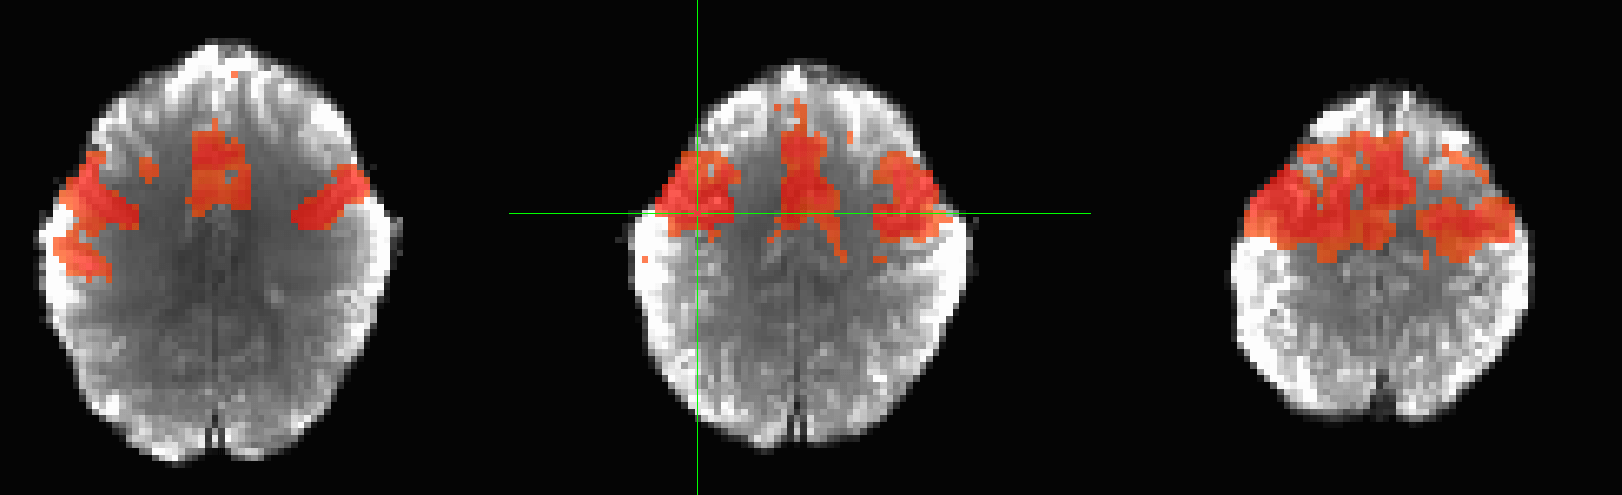

BOLD signal: "Functional Networks"

Biswal et al., 1995 (Magn. Reson. Med.)

Pearson correlation:

Whole brain functional connectivity

Huang et al., 2018 (Proc. IEEE)